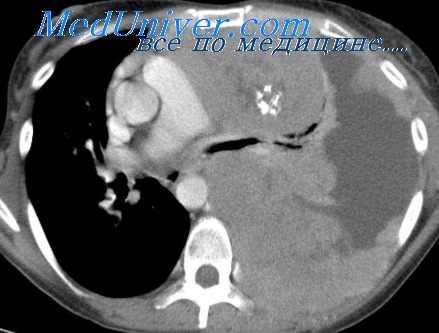

(Слева) КТ с контрастированием, аксиальный срез: определяется крупное поликистозное двустороннее образование шеи, почти полностью смещающее все нормальные ткани по окружности. У этого двухдневного новорожденного томограмма была получена для оценки распространения образования и планирования чрескожной склеротерапии.

3. КТ при лимфангиоме:

• Образование с четкими или нечеткими контурами

• Дольчатое с гиподенсными кистозными областями:

о Кистозные области не накапливают контраст

• Могут прорастать или смещать соседние органы

• Кальцификаты встречаются редко